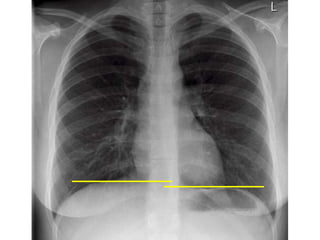

Identify both costophrenic angles and lung apices

Name

Date Orientation

Adequate

inspiration

9 ribs

posteriourly

Exposure

Adequate tissue

penetration

Adequate anatomical exposure

Gastric air bubble

Rotation